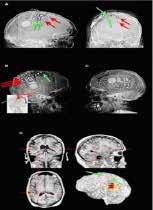

Sub-dural grid electrodes on a human brain in an operative room to map vital brain functions and record seizures for precise localization of seizure onset zone before surgery. PHOTOS: PROVIDED BY FALCON ADVANCED NEUROLOGY & EPILEPSY FREEDOM CENTER

The responsive neurostimulation (RNS) system to diagnose and treat seizures is one of the breakthrough advances in epilepsy care. PHOTOS: PROVIDED BY FALCON ADVANCED NEUROLOGY & EPILEPSY FREEDOM CENTER